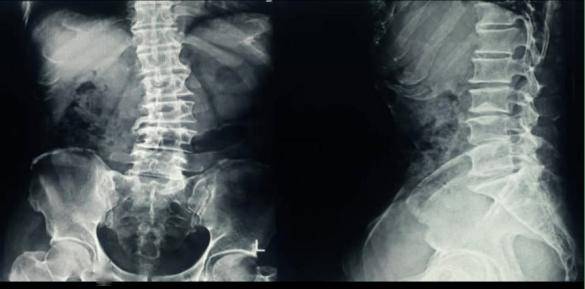

X线检查

优势:

简便、直观,是最常用的初步检查方法。可以观察骨骼的大体形态、结构以及是否存在骨折等明显病变。对骨折的诊断价值高,能清晰显示骨折的部位、类型和移位情况,对于因骨质疏松导致的常见骨折如椎体压缩骨折、髋部骨折等有重要的诊断意义。

不足之处:

对早期骨质疏松不敏感:在骨质疏松早期,骨量丢失尚未达到一定程度时,X线难以发现明显异常。只有当骨量丢失超过30%左右时,X线片上才可能出现骨质疏松的征象。